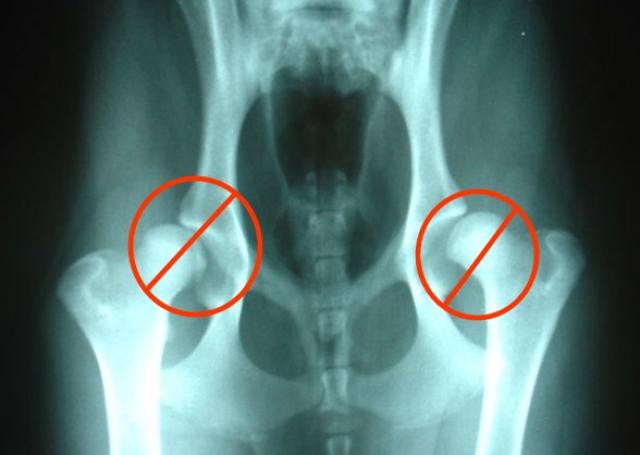

Xray of cat hip pelvis and leg back right leg 349. You only need an X-ray if your doctor recommends it. The cost of treating a cats broken leg depends on the severity of the fracture and the vet you go to.